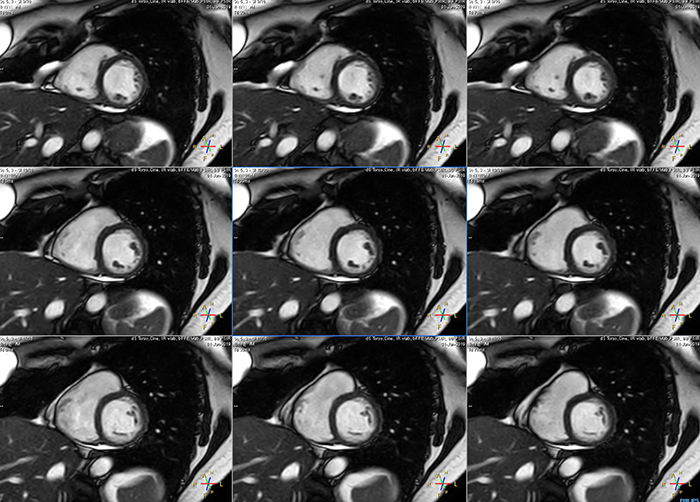

Short breath hold cardiac cine

MCVI Ambition Short breath hold cardiac cine

These are some images of a cardiac cine scan with a short breath-hold time. A high temporal resolution provides a smooth cine, which helps in assessing heart function. Ingenia Ambition.